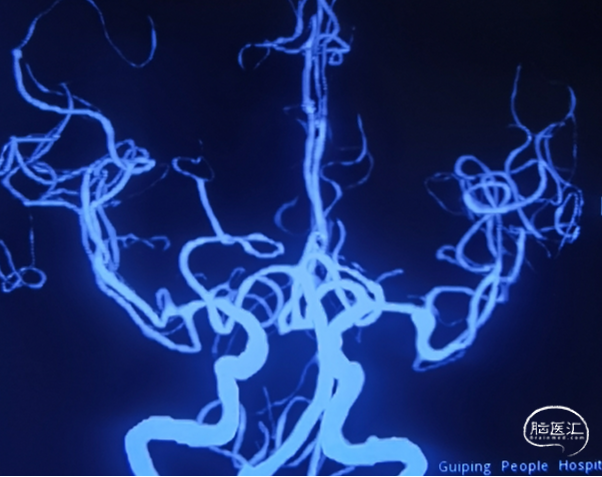

DSA

平均宽度(4.7+3.5)=4.1mm,最小深度3.4mm,选择SL6x2

CBCT

术后CT